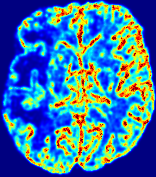

Figure 3: PIANO feature maps for one stroke patient, where the lesion is located in the left hemisphere. Top row: segmented stroke lesion region (white) on different slices, obtained from ISLES 2017. The corresponding slices for the PIANO feature maps are shown in the following rows.

For a better insight into an estimated velocity field 𝐕𝐕{\bf{V}} and diffusion field 𝐃𝐃{\bf{D}}, we compute the following maps: (1) 𝐕rgbsubscript𝐕𝑟𝑔𝑏{\bf{V}}_{rgb}: Color-coded orientation map of 𝐕=(Vx,Vy,Vz)T𝐕superscriptsuperscript𝑉𝑥superscript𝑉𝑦superscript𝑉𝑧𝑇{\bf{V}}=(V^{x},V^{y},V^{z})^{T}, obtained by normalizing 𝐕𝐕{\bf{V}} to unit length and mapping its 3 components to red, green, blue respectively; (2) 𝐕2subscriptnorm𝐕2\|{\bf{V}}\|_{2}: 222 norm of 𝐕𝐕{\bf{V}}; (3) D𝐷D: scalar field in Eq. 5.

Fig. 3 and Fig. 4 show the PIANO feature maps estimated from two ISLES 2017 patients: all are highly consistent with the lesion in both cases. Details of the blood flow trajectories are revealed in 𝐕rgbsubscript𝐕𝑟𝑔𝑏{\bf{V}}_{rgb} by the ridged patterns and the sharp changes of colors in the unaffected (right) hemisphere, while the flat patterns appearing within the lesion provide little directional information about the velocity and indicate low velocity magnitudes. Velocity magnitudes are more directly visualized via 𝐕2subscriptnorm𝐕2\|{\bf{V}}\|_{2}, from which one can easily locate the lesion where 𝐕2subscriptnorm𝐕2\|{\bf{V}}\|_{2} is low. D𝐷D also indicates lower diffusion values in the lesion, though with less contrast potentially due to the fact that it captures the accumulated effect of CA diffusion at the voxel-level.